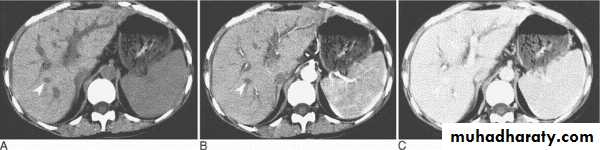

Patient with multiple sclerosis with plaques of demyelination shown on (A) fast spin-echo (FSE) proton density; (B) FSE T2; and (C) FSE FLAIR. There is no discernible abnormality on T1-weighted images without contrast